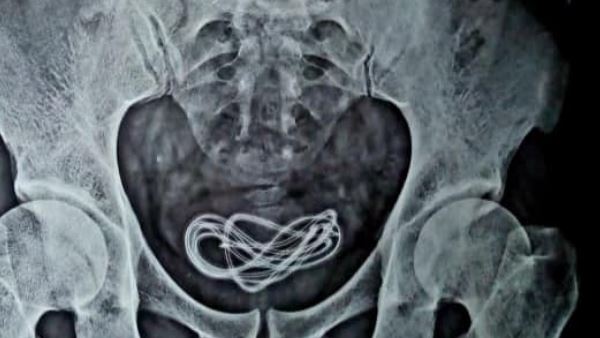

नई दिल्ली। असम के गुवाहाटी में एक अजीब मामला सामने आया है। यहां एक शख्स ने निजी अंग में मोबाइल का चार्जर घुसा लिया। उसके पेट में दर्द हुआ तो डॉक्टरों ने जांच में पाया कि उसके मूत्राशय में तार जैसा कुछ है। ऑपरेशन कर डॉक्टरों ने करीब एक मीटर लंबा मोबाइल चार्जर का केबल शख्स के ब्लेडर से निकाला। मामले पर ना सिर्फ आम लोग हैरानी जता रहे हैं बल्कि डॉक्टर भी हैरत में हैं।

सर्जन डॉक्टर वली इस्लाम ने फेसबुक पर इस ऑपरेशन की तस्वीरें और वीडियो शेयर किय है। जानकारी के मुताबिक, गुवाहाटी में रहने वाले 30 साल का शख्स डॉक्टर के पास पेट दर्द की शिकायत लेकर आया था। उसने डॉक्टरों को बताया था कि उसने गलती से मोबाइल चार्जर का केबल निगल लिया है। डॉक्टर ने जब युवक के पेट को स्कैन किया तो उन्हें कुछ भी नहीं मिला लेकिन जब मूत्राशय का एक्सरे किया गया तो वहां केबल होने का पता चला।

डॉक्टर वली ने फेसबुक पर लिखा है। बतौर सर्जन अपने 25 साल के करियर में पहली ऐसी सर्जरी कर रहा हूं। इस तरह का मामला पहली बार देखा है। मरीज ने गलती से उसने हेडफोन केबल निगल लेने की बात कही थी लेकिन हमें उसके ब्लेडर से केबल मिला। ये उसने निजी अंग में से अंदर डाली है। डॉक्टर का कहना है कि मरीज ने शराब के नशे की हालत में ऐसा किया है। वहीं उसकी दिमागी हालत भी पूरी तरह से ठीक नहीं है।

डॉक्टरों ने बताया है कि मरीज की सर्जरी तो सफल रही है और वो तेजी से ठीक हो रहा है।वहीं ऑपरेशन का इस घटना का वीडियो और कुछ तस्वीरें जो डॉक्टर वली ने शेयर की हैं। तेजी से वायरल हो रही हैं। कई लोगों ने इन पर कमेंट किए हैं। लोग भी घटना को जानकर हैरान हैं और विश्वास नहीं कर पा रहे हैं।